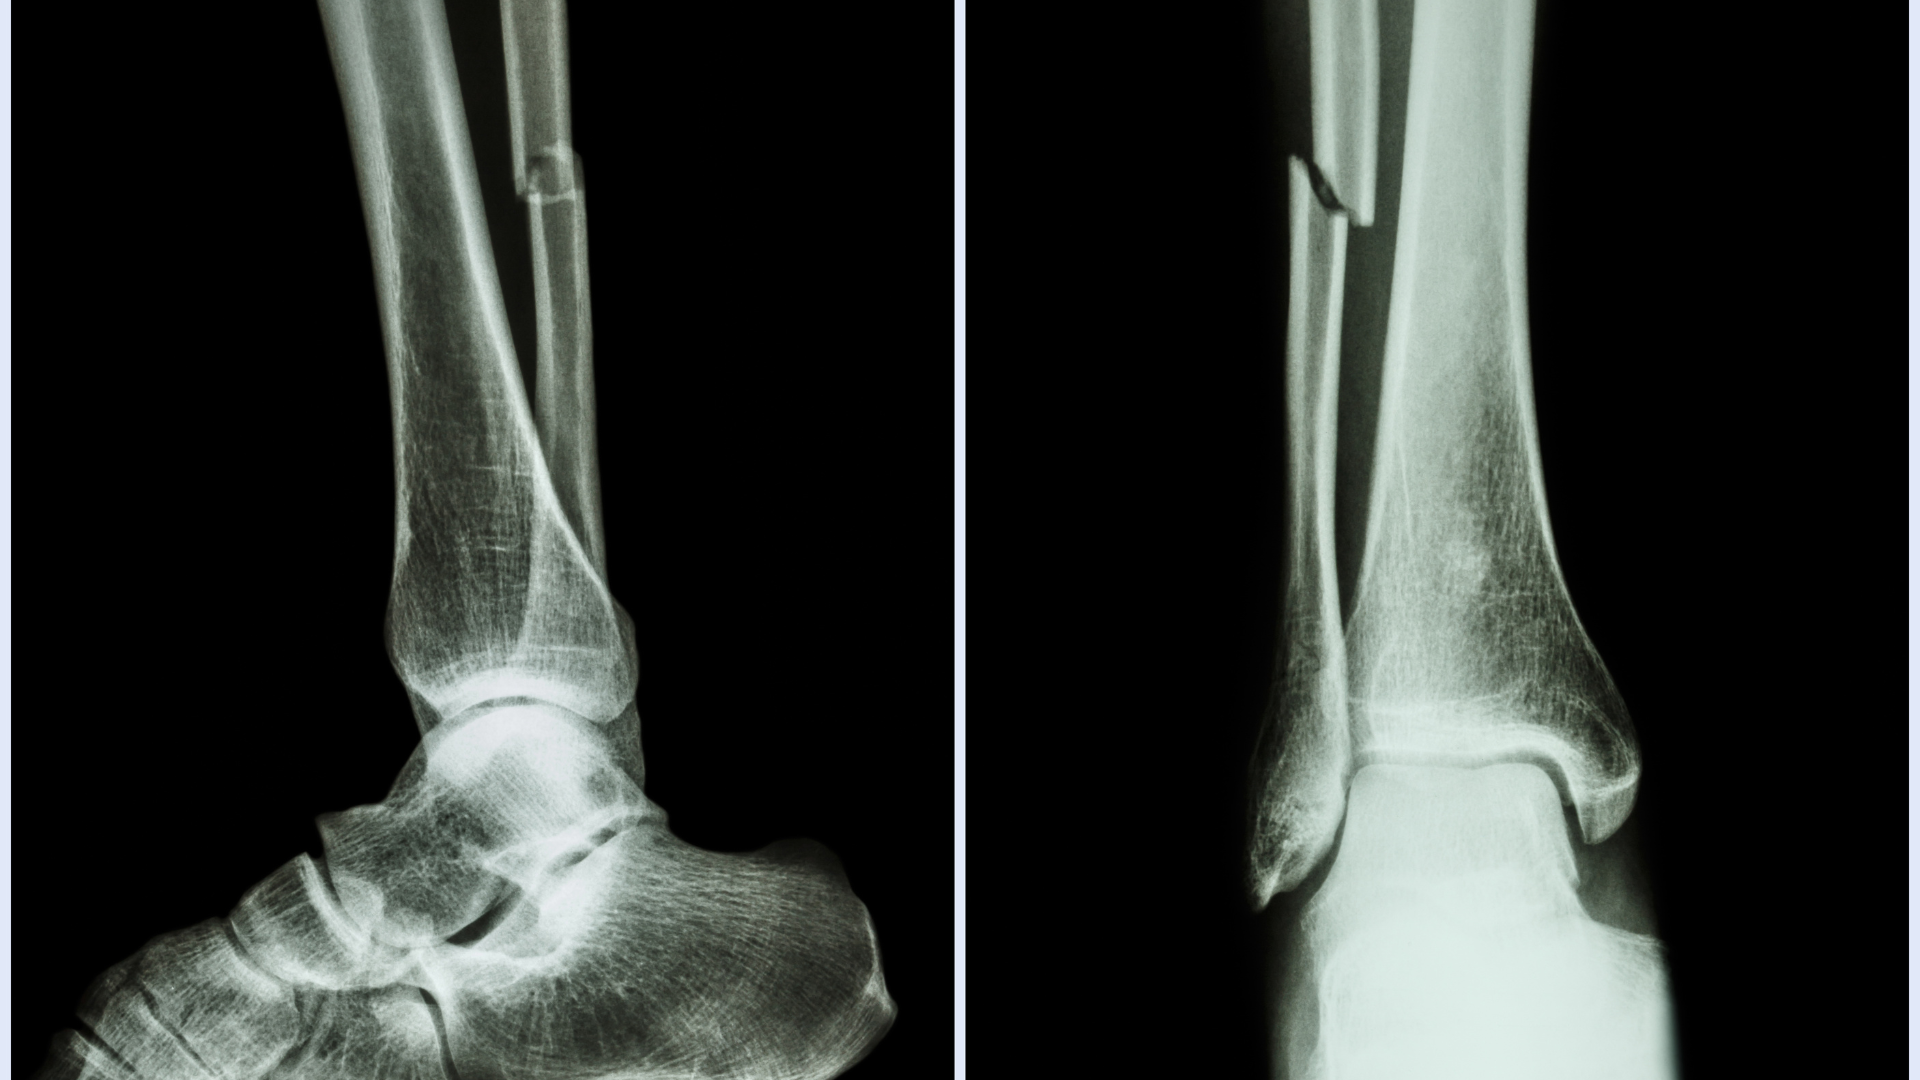

Chẩn đoán hình ảnh giúp xác định vị trí và mức độ gãy. X-quang cẳng chân là bước cơ bản, trong khi CT scan hoặc MRI được sử dụng khi nghi ngờ gãy phức tạp hoặc tổn thương mô mềm, giúp bác sĩ đưa ra phương án điều trị chính xác.